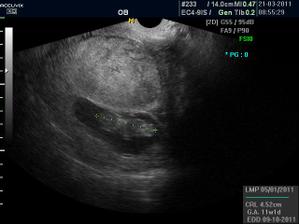

Pidižva č.2 a č.3... :o)

ahojky, no krásnýýýý, takže je to pravda, jak jsi mi psala, jupííí, jen houšť dvojčat 🙂)))))

@elis.1 elí je to krásný, ale to víš, trošku se bojím, aby bylo všechno v pořádku. Ale jsou nádherný a jak se mrskali...:o))) mi budeš muset dávat rady jak na dvojčata...:o)))